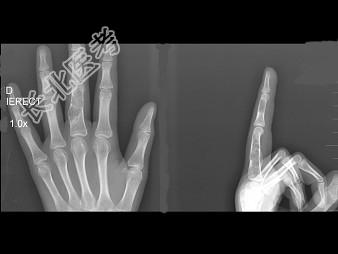

- 单项选择题男,15岁, 左侧中指局部肿胀,无压痛, 关节活动无明显异常,结合图像, 最可能诊断是 ( )

B、内生软骨瘤